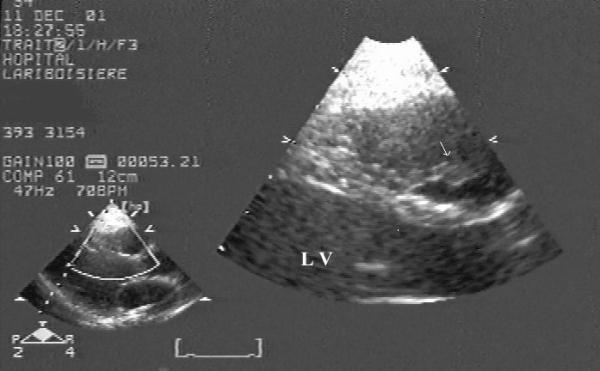

A case of a 31-year-old woman with intravenous drug abuse who had a right-sided vegetation attached to the muscular bundle of the right ventricle is presented. Transthoracic echocardiography revealed a vegetation in the right ventricular outflow tract. Transesophageal echocardiography clearly showed that the 1.8 cm vegetation was not adherent to the pulmonary valve but attached to a muscular bundle.

本文报告一例31岁静脉吸毒女性患者,其右侧心室肌束上附着有赘生物。经胸超声心动图显示右心室流出道有一赘生物。经食管超声心动图清楚地显示,1.8厘米的赘生物未附着于肺动脉瓣,而是附着于一束肌肉上。